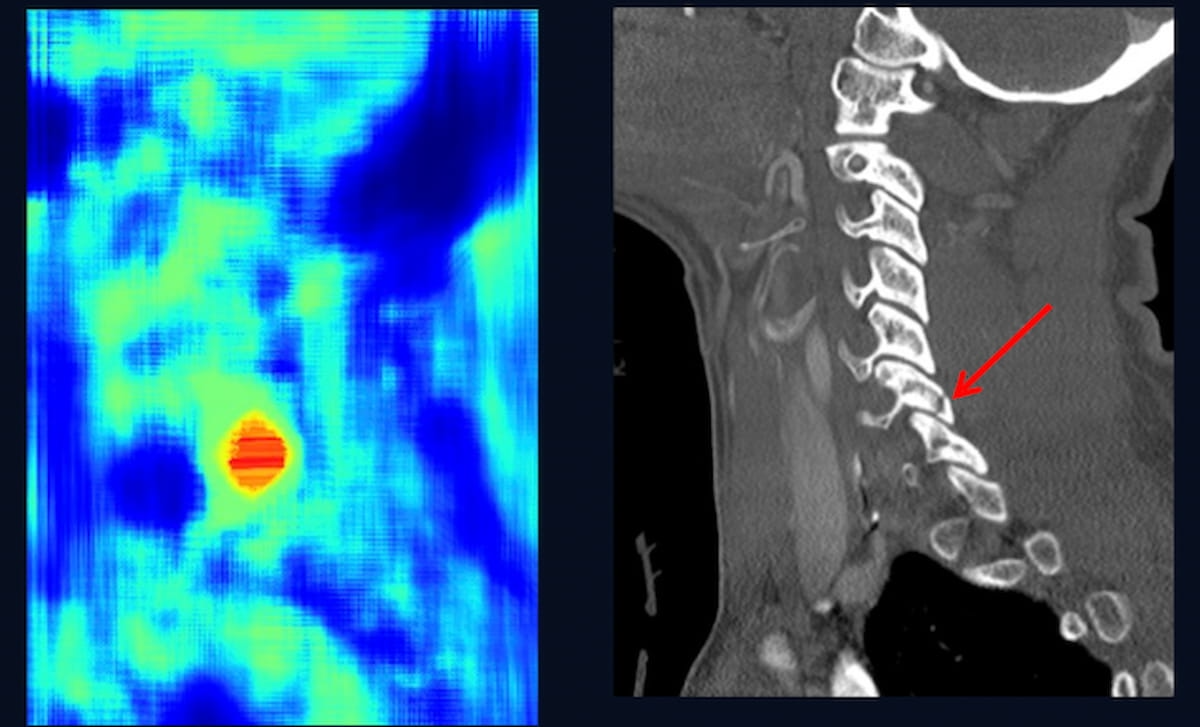

In a recent interview, Atul Gupta, M.D. discussed the evolution and potential impact of Fiber Optic RealShape (FORS) technology, which uses light instead of radiation to facilitate real-time 3D imaging that may lead to significant efficiencies with complex aortic procedures.